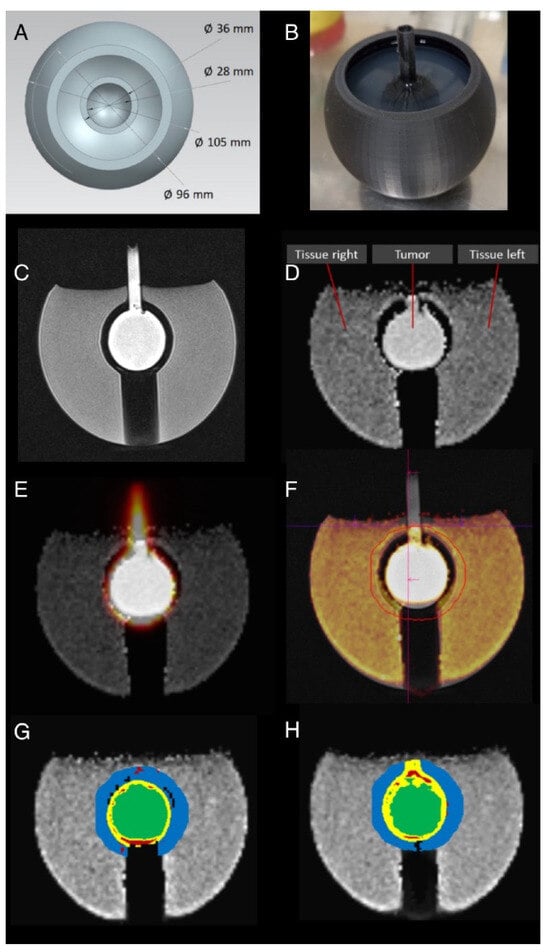

2.1. Phantom Generation

2.3. Tumor Phantom

2.4. Phantom MR and PET Measurements

3.3. Sphere and Tumor Phantoms